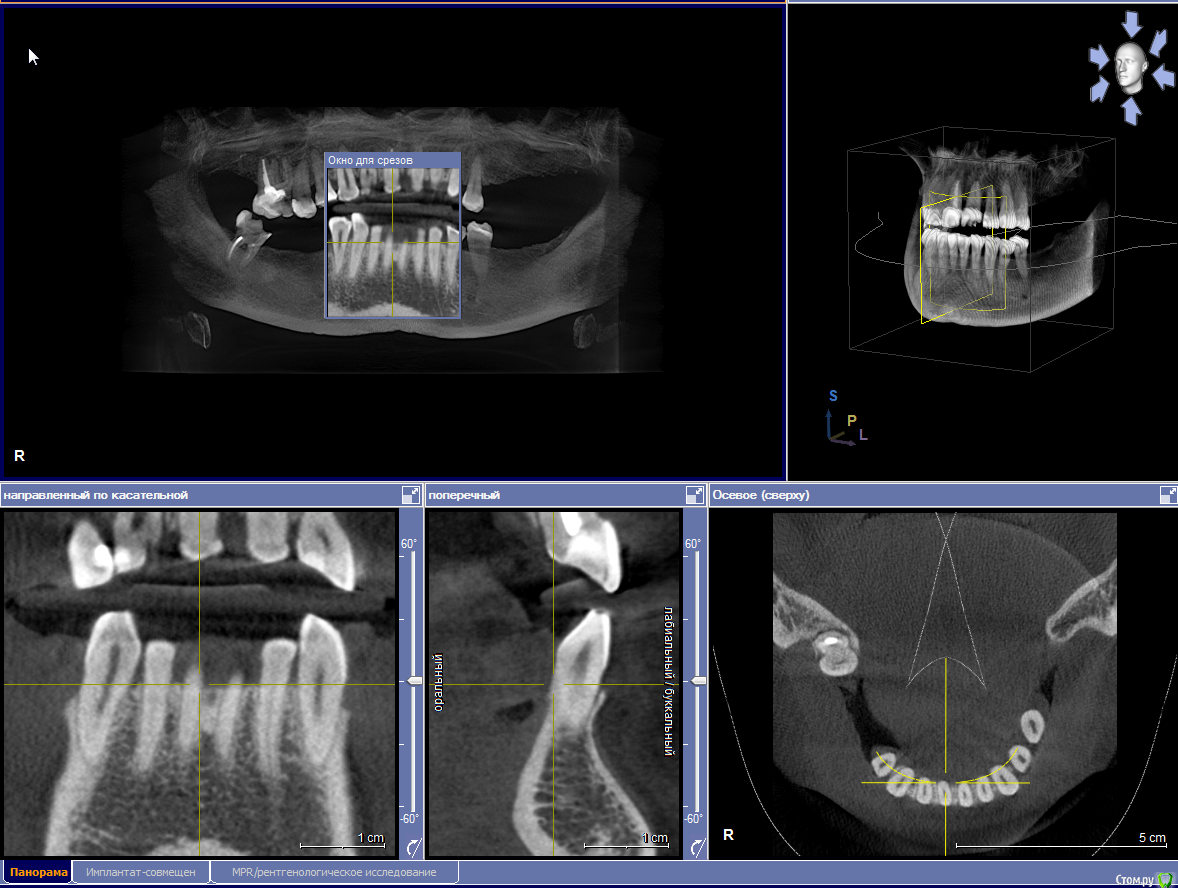

elesilchenko@yandex.ru Опубликовано 18 октября, 2016 Поделиться Опубликовано 18 октября, 2016 Здравствуйте! Подскажите, пожалуйста, возможна ли дентальная имплантация на НЧ без применения костной пластики? И возможно ли спасти зубы с кистами на ВЧ ?Результаты КТ: http://files.mail.ru/1F70A64348084F03ACC722DA9E76BD2B Ссылка на комментарий

elesilchenko@yandex.ru Опубликовано 18 октября, 2016 Автор Поделиться Опубликовано 18 октября, 2016 Добрый вечер! Я в процессе выбора, кто предлагает базальную имплантацию внизу (ВЧ я пока не рассматриваю к имплантации) , кто съемные протезы это на НЧ. По поводу ВЧ тоже разные мнения: 1. Можно полечить, т.к. проблемы с эндодонтией 16 и 12, где небольшой воспалительный процесс.2. 16 удалить, 12 попытаться полечить. Сунус-лифтинга и костной пластики боюсь. Ссылка на комментарий

IvanK Опубликовано 18 октября, 2016 Поделиться Опубликовано 18 октября, 2016 Судя по скудной информации из скриншотов:кости , скорее всего, будет достаточно Вам нужно найти Врача, которому доверяете и довериться) Сходите на пару-тройку очных консультаций Ссылка на комментарий